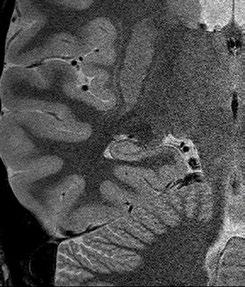

Fig 1: Next generation MRI is being used to gather data on brain tissue volumes Dr. Steve McNally

From this season at Manchester United Football Club, we have started to gather data by using MRI (see fig 1) to measure volumes of brain tissue in specific areas, to monitor for a decrease in volumes over time. If the volumes become unusual or deviate from the norms that we would expect, it may help us identify early changes of CTE that need closer monitoring. This is a new, long-term data gathering study in our cohort of players that has been facilitated with the new next generation MRI3 now in place at our medical centre.

Fig 2: Very small fibre tears identified using high resolution MRI